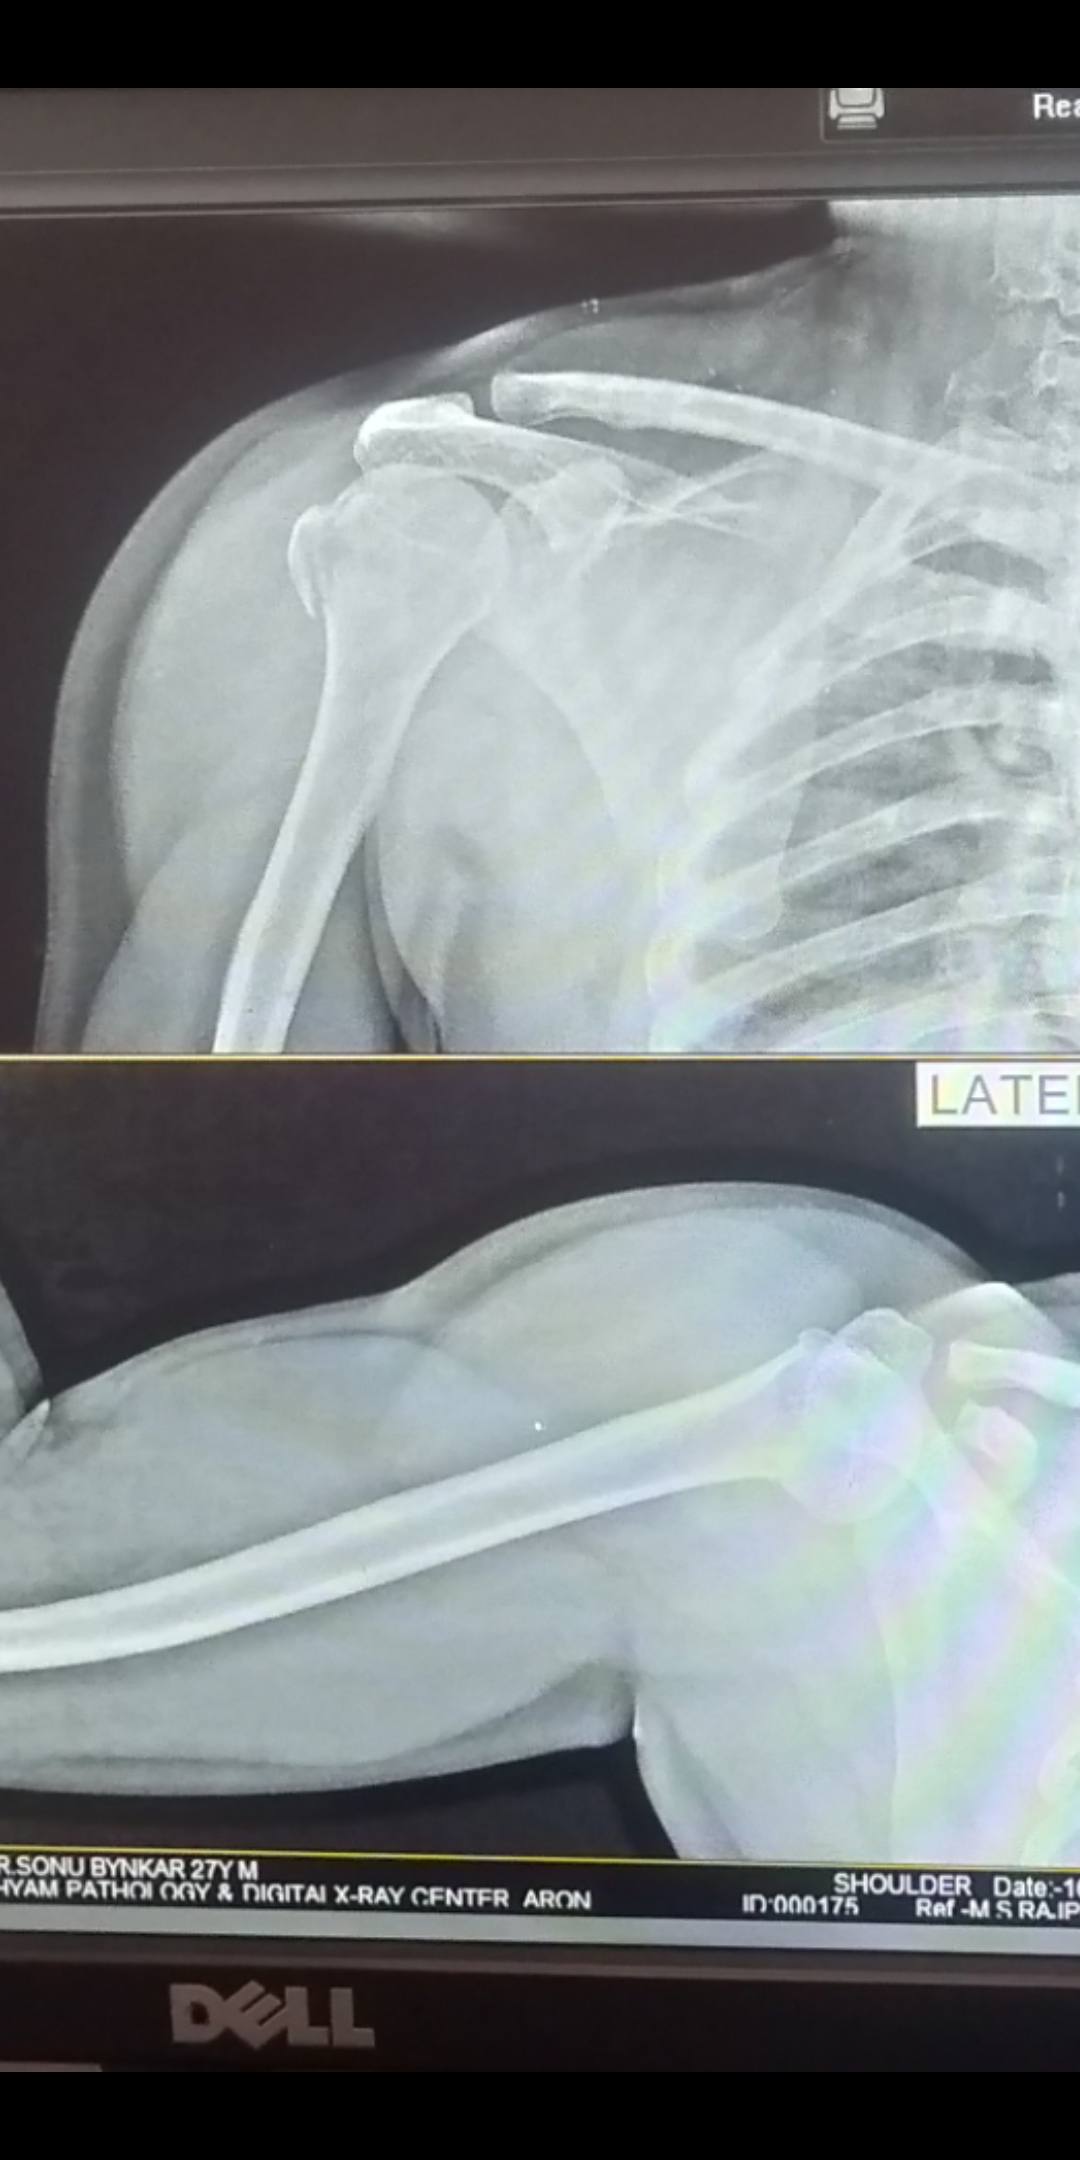

हिप फ्रैक्चर: हिप फ्रैक्चर वृद्ध वयस्कों में एक आम समस्या है। वे गिरने या आघात के कारण होते हैं, और गंभीर दर्द और गतिशीलता के मुद्दों का कारण बन सकते हैं।

चोटें: कूल्हे की चोटें, जैसे हिप फ्रैक्चर, लंबे समय तक कूल्हे की समस्या पैदा कर सकती हैं।